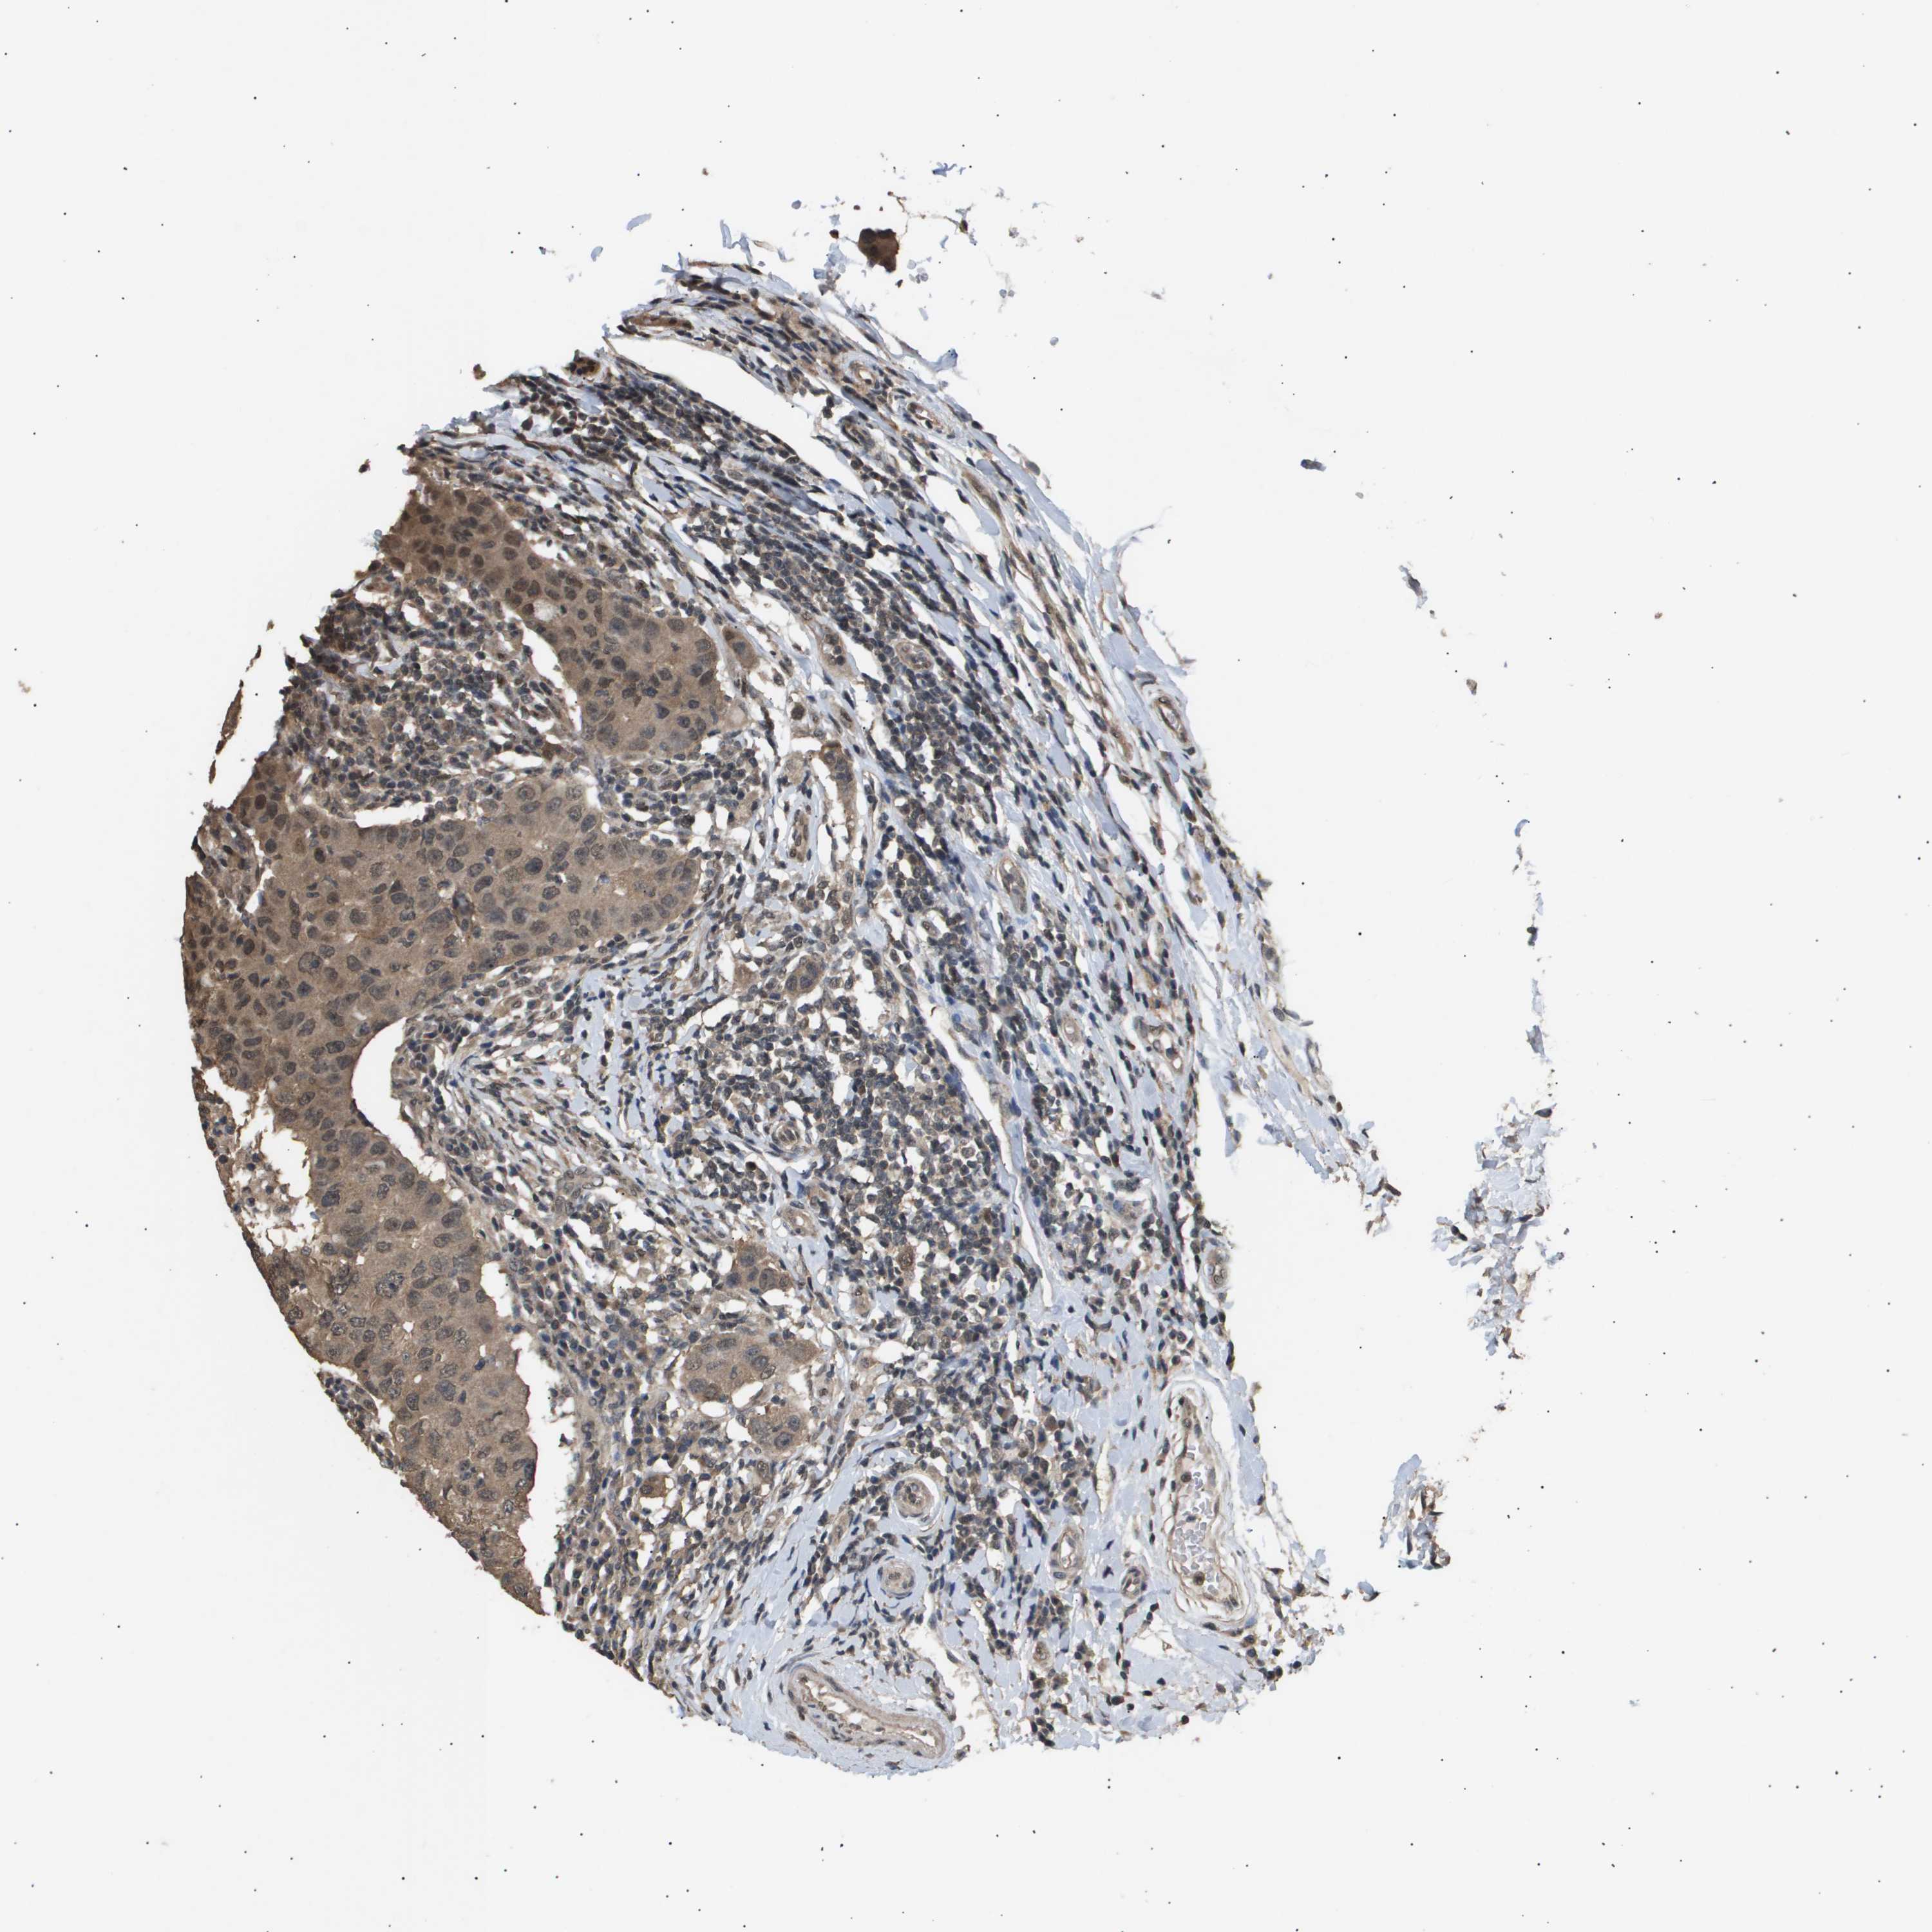

CANCER BREAST CANCER Show tissue menu

BRCA TCGA BRCA VALIDATION PROTEIN EXPRESSION

ANTIBODIES

AND

VALIDATION